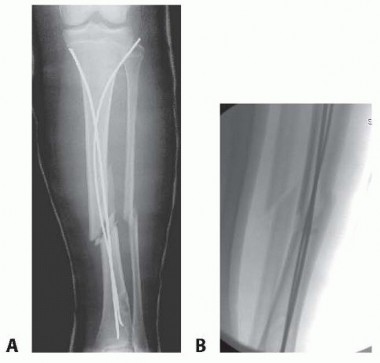

TECH FIG 1

•

A.

External fixation in a patient with a compartment syndrome.

Arrows

mark the proximal and distal growth plates. The proximal pins start fairly distally to avoid the tubercle physis.

B.

In this patient, an external fixator was used for a grade 2 open fracture treated with delayed closure. The patient also had a degloving injury requiring a flap and skin graft over the medial ankle. The frame was extended to the first metatarsal to immobilize the foot during healing. Although somewhat bulky, the “double stack” configuration of the frame allows for easy dynamization.